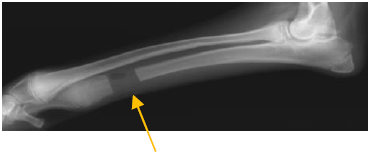

1. ボルゾイの前足の骨折(橈尺骨骨折)

プレートという器具を使って骨を固定したところです。 骨の折れ方のパターンや、大型犬であることを考慮して、 プレートを2枚使用して治療しています。 |